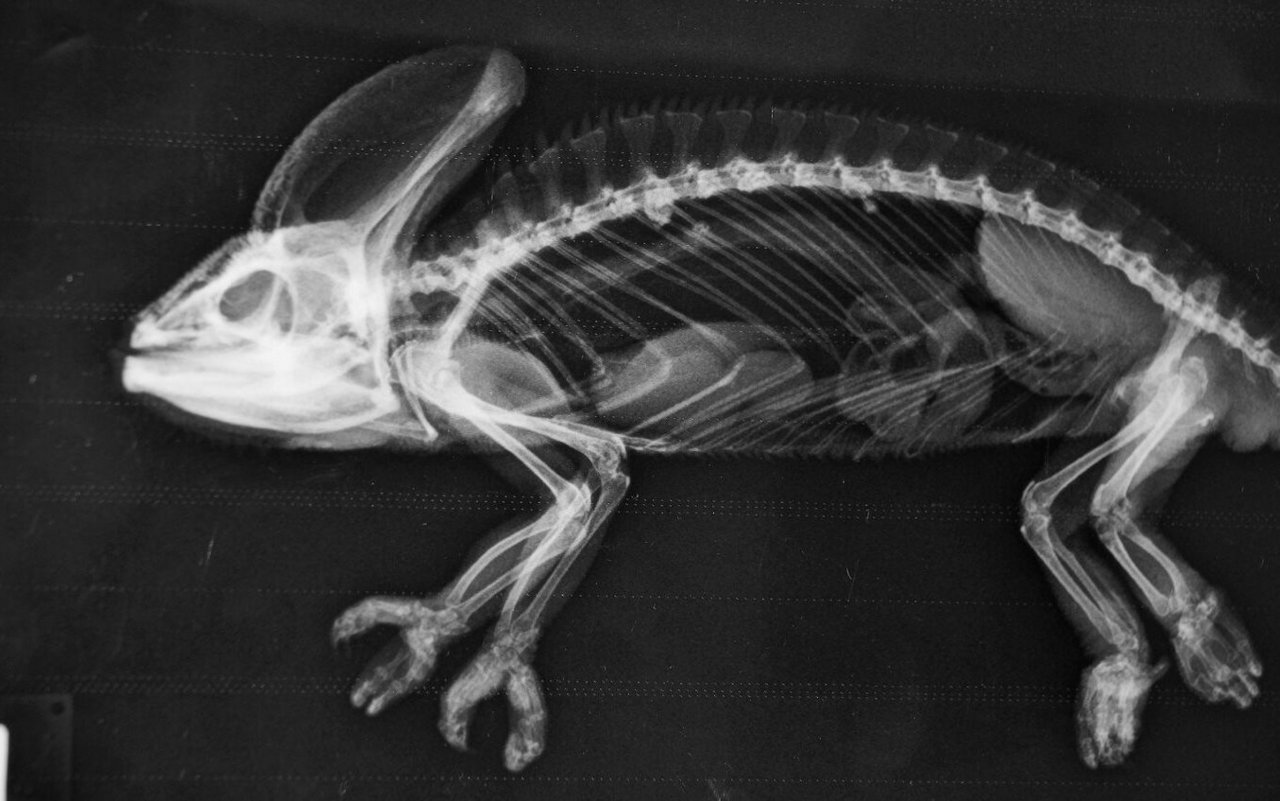

Einfacher auf dem Röntgentisch fixiert werden als ein Fisch kann eine Schildkröte. «Wir setzen sie auf eine Platte», sagt Christian Wenker. Bevor sie den Kopf aus dem Panzer schiebt, ist das Röntgenbild schon gemacht. Wie bei Vögeln kommt bei Reptilien Legenot vor, die mittels eines Röntgenbildes festgestellt werden kann. Damit Echsen wie Leguane nicht von der Röntgenplatte krabbeln, gibt es einen Trick. «Wir drücken kurz sanft und gleichzeitig auf die Augäpfel, dies führt über einen Vagusreflex zu einem betäubungsähnlichen Zustand», sagt der Zootierarzt.

[IMG 5]